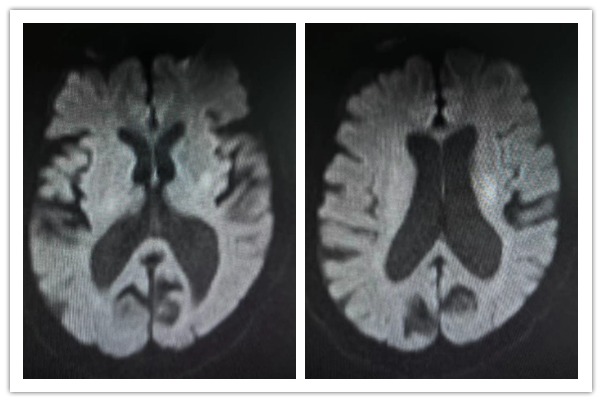

0點(diǎn)24分,張女士在灃東院區(qū)腦病病區(qū)進(jìn)行阿替輔酶靜脈溶栓,DNT時(shí)間35分鐘。1點(diǎn)30分,溶栓治療結(jié)束,患者無明顯不適,生命體征平穩(wěn),NIHSS評(píng)分6分,完善顱腦DWI、MRA,溶栓治療成功。

顱腦DWI、MRA